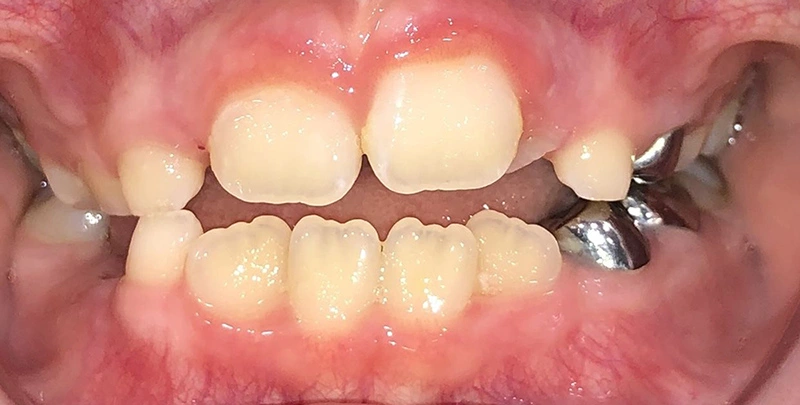

Actual Patient: Bailey

Img Before 3 1 Img After 3 1

Severe “Overbite”, BUCK TEETH, Narrow Jaws, Severe Deep Bite

Bailey Before 1 Beliy after img

7.5 months

Front View

Top View

Right & Left Sides